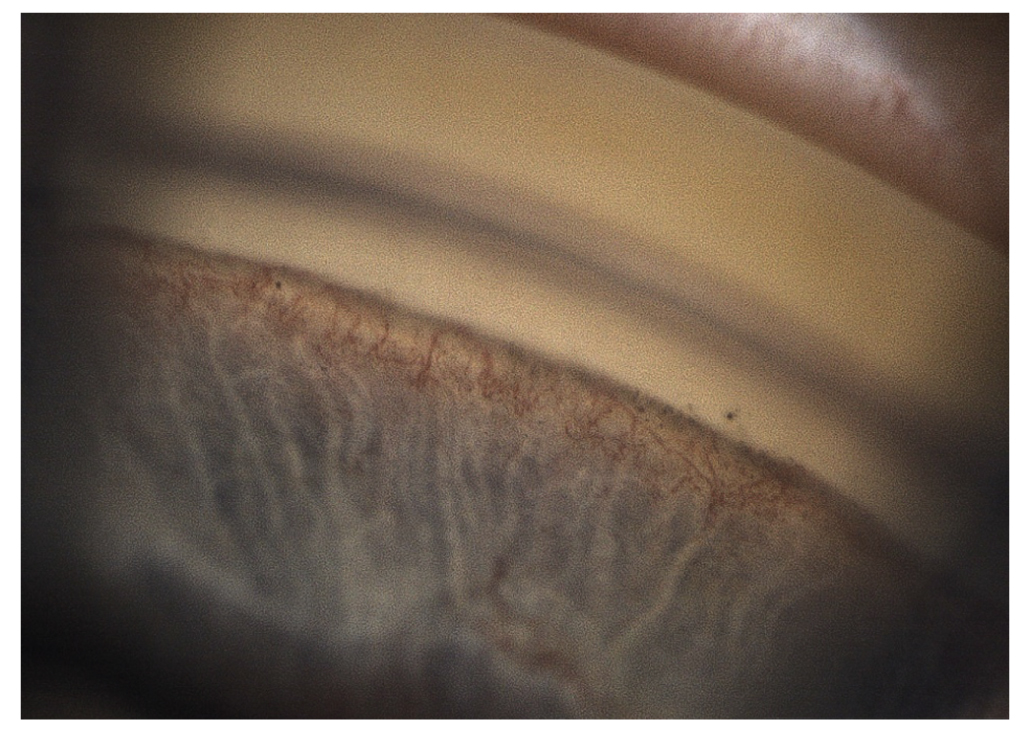

Биомикроскопически во всех случаях выявлен рубеоз радужки различной степени выраженности. При гониоскопии у 6 (18,8%) пациентов угол передней камеры был открыт, в его структурах визуализировались новообразованные сосуды (рис. 2); в 26 (81,3%) случаях угол передней камеры был закрыт синехиями и неоваскулярной мембраной различной протяженности.

Рис. 2. Электронная гониоскопия: неоваскуляризация структур угла передней камеры. / Fig. 2. Electronic gonioscopy: neovascularization of the structures of the anterior chamber angle.